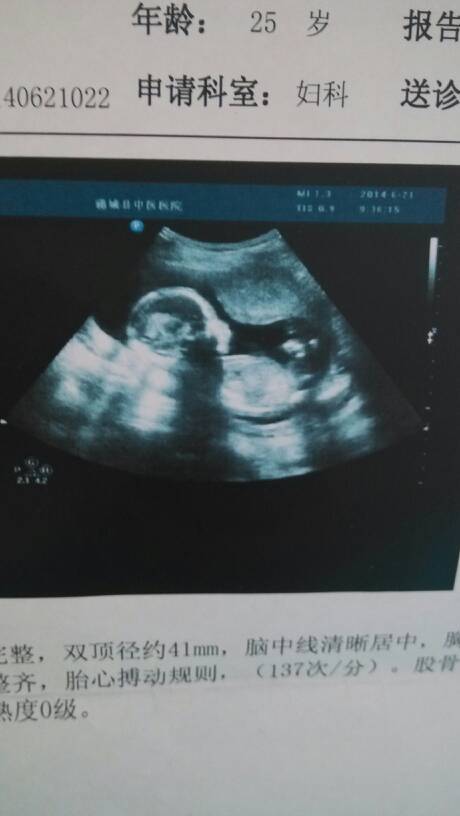

十八周零三天 我看不懂…谁能看懂给我说说 十八周零三天 我看不懂……谁能看懂给我说说 点击展开 嘟嘟 2014-06-23 15:21 为您推荐: 其他回答 不要客气,我会竭诚为您服务的。 博爱医生88 2014-06-23 15:32 那看不出来的,太小了,也不会给你看的。 博爱医生88 2014-06-23 15:28 根据你说的情况,B超不是很完整的报告,不知道你要咨询什么问题。 博爱医生88 2014-06-23 15:25 相关问题 我怀孕十八周零三天要不要买钙片吃呢? 我是3月10号最后一次月经,请问我那现在是不是怀孕十三周零三天了呢